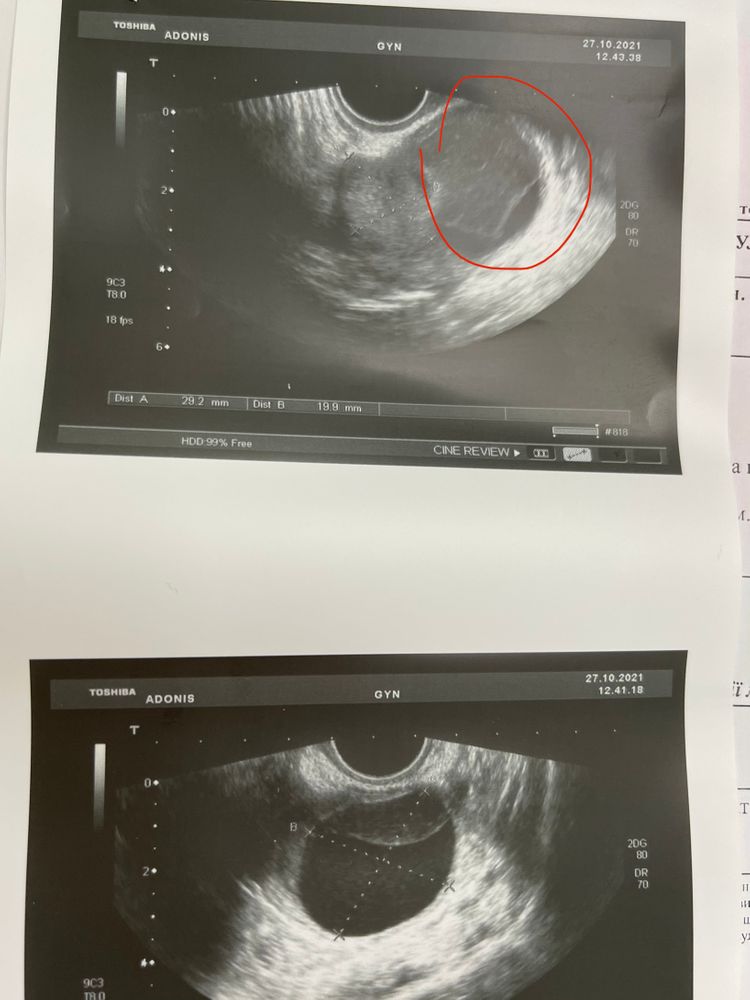

При таких тестах О была - на узи киста ЖТ на 17ДЦ 38мм. Судя по БТ - где-то на 12ДЦ. На Б не надеемся, так как кисты ЖТ три раза подряд, и явно есть проблемы с О. И эндик не секреторный(

Киста ЖТ должна быть неровной, а вот киста фоолликулярная именно ровная, гладкая. Точно ЖТ киста? И если да, то при ней беременномть реальна и ничего страшного и даже частенько у многих при беременности она от повышенного Прога бывает. А то, что эндик плохой вызывает сомнения в Б и в кисте ЖТ.

Светлана Никиткова, точно, с кровотоком , на верхнем снимке видно структуру жт , а снизу на снимке как Ре сказала «кистозная часть жт», типа жидкость. Вообщем как-то неправильно что-то работает у меня в процессе овуляции 😵💫 будем следить в следующий циклах, с уколом хгч

Женя Ветлова, кистозная часть, вероятно имелось ввиду уровень жидкости. Но если посмотрите внимательно, это наслаивается край то-ли матки не понятно. Смотрите этот предполагаемый уровень продолжается справа дальше границы "кисты". Больше похоже на ф.кисту походу. Может сходите ещё раз на узи к другому в другую клинику? Но не говоря о результате первом.

Di Di, не совсем понимаю 😀 но если имеете ввиду нижний снимок , и часть серую как бы сверху - то это ЖТ. Верхний снимок - это эта часть под другим углом 😀 ой, я уже в трёх местах делала узи , три цикла подряд одинаковые кисты жт вырастают. Одинаково выглядят , часть жт и часть жидкость 😵💫 доплер видит кровоток